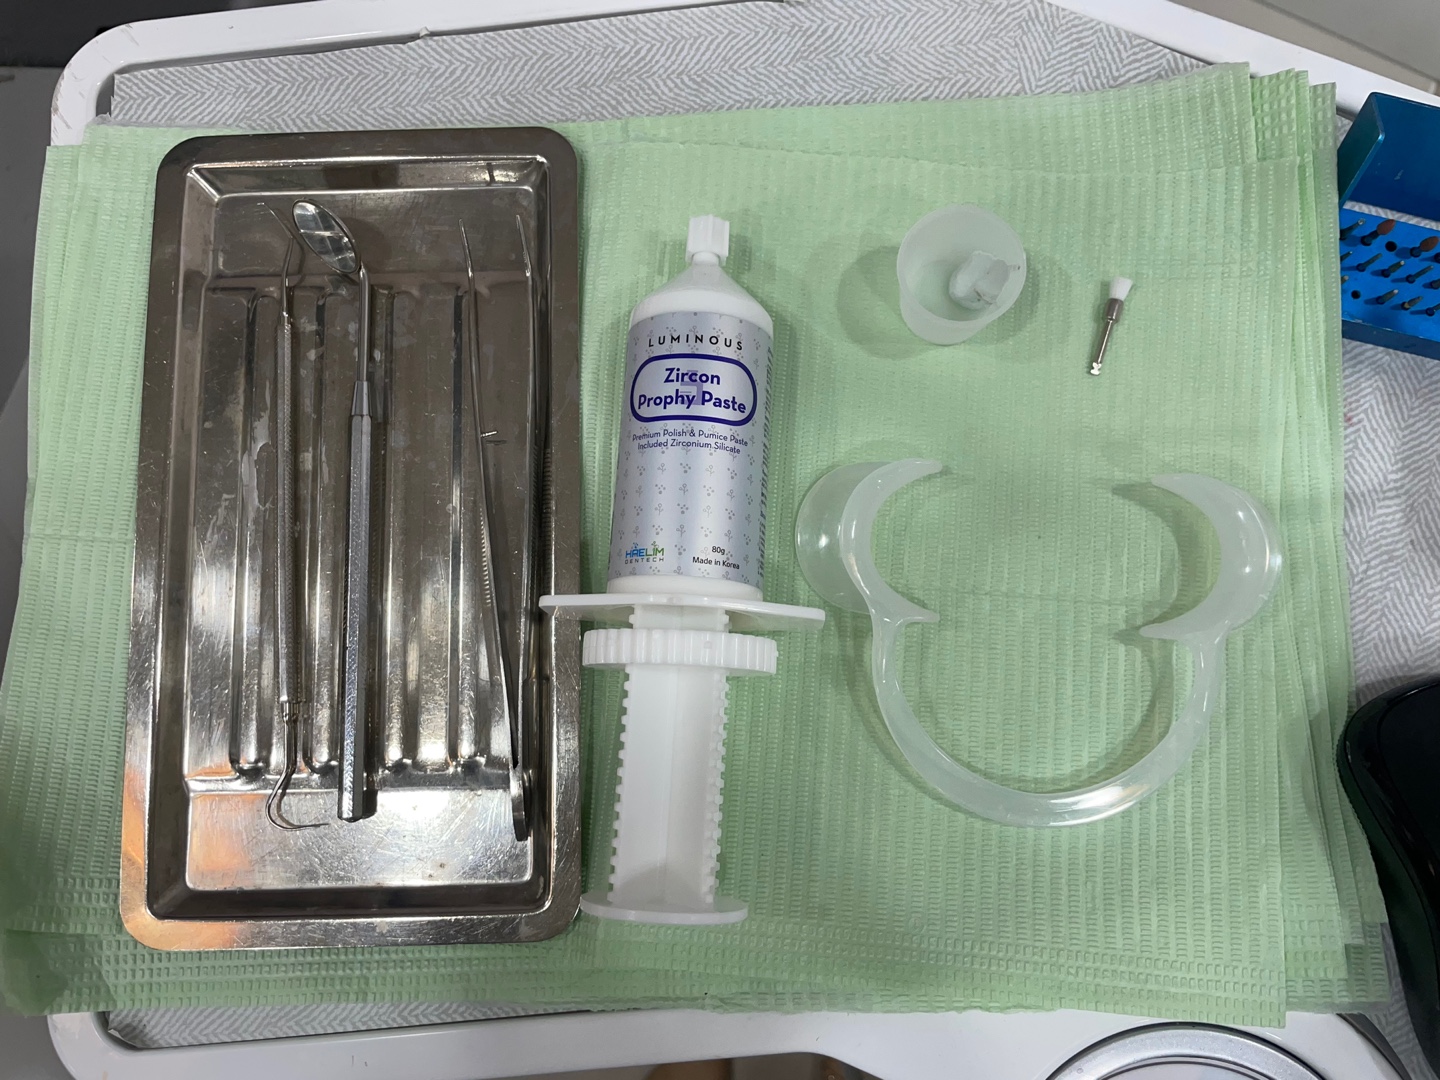

첫날 상당히 긴 시간동안 환자분이 협조해 주셔서

첫 단추를 잘 채웠습니다.